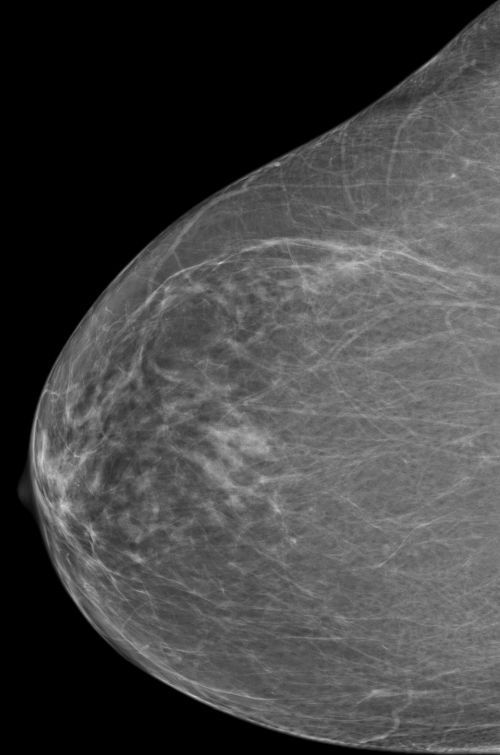

ACR-Klassifikation der Brustdichte in der Mammographie

Die ACR-Klassifikation der Brustdichte in der Mammographie ist ein System zur Einteilung der Brustgewebe in vier Kategorien, die von A bis D reichen. In Deutschland wird der anstatt ACR der Begriff Beurteilbarkeitsstufe verwendet.

Die Kategorie A steht für eine fast vollständig fettreiche Brust, die Kategorie B für eine überwiegend fettreiche Brust mit einigen fibroglandulären Bereichen, die Kategorie C für eine heterogen dichte Brust mit mehreren fibroglandulären Bereichen und die Kategorie D für eine extrem dichte Brust mit sehr wenig Fettgewebe.

Die Brustdichte ist ein wichtiger Faktor für die Erkennung von Brustkrebs, da dichtes Gewebe die Beurteilbarkeit der Mammographie erschweren und mögliche Tumoren verdecken kann. Die ACR-Klassifikation der Brustdichte in der Mammographie hilft den Radiologen, die Aussagekraft der Mammographie zu beurteilen. Je dichter das Drüsengewebe, desto sinnvoller ist eine zusätzliche Methode wie Mamma-Sonographie oder Mamma-MRT.